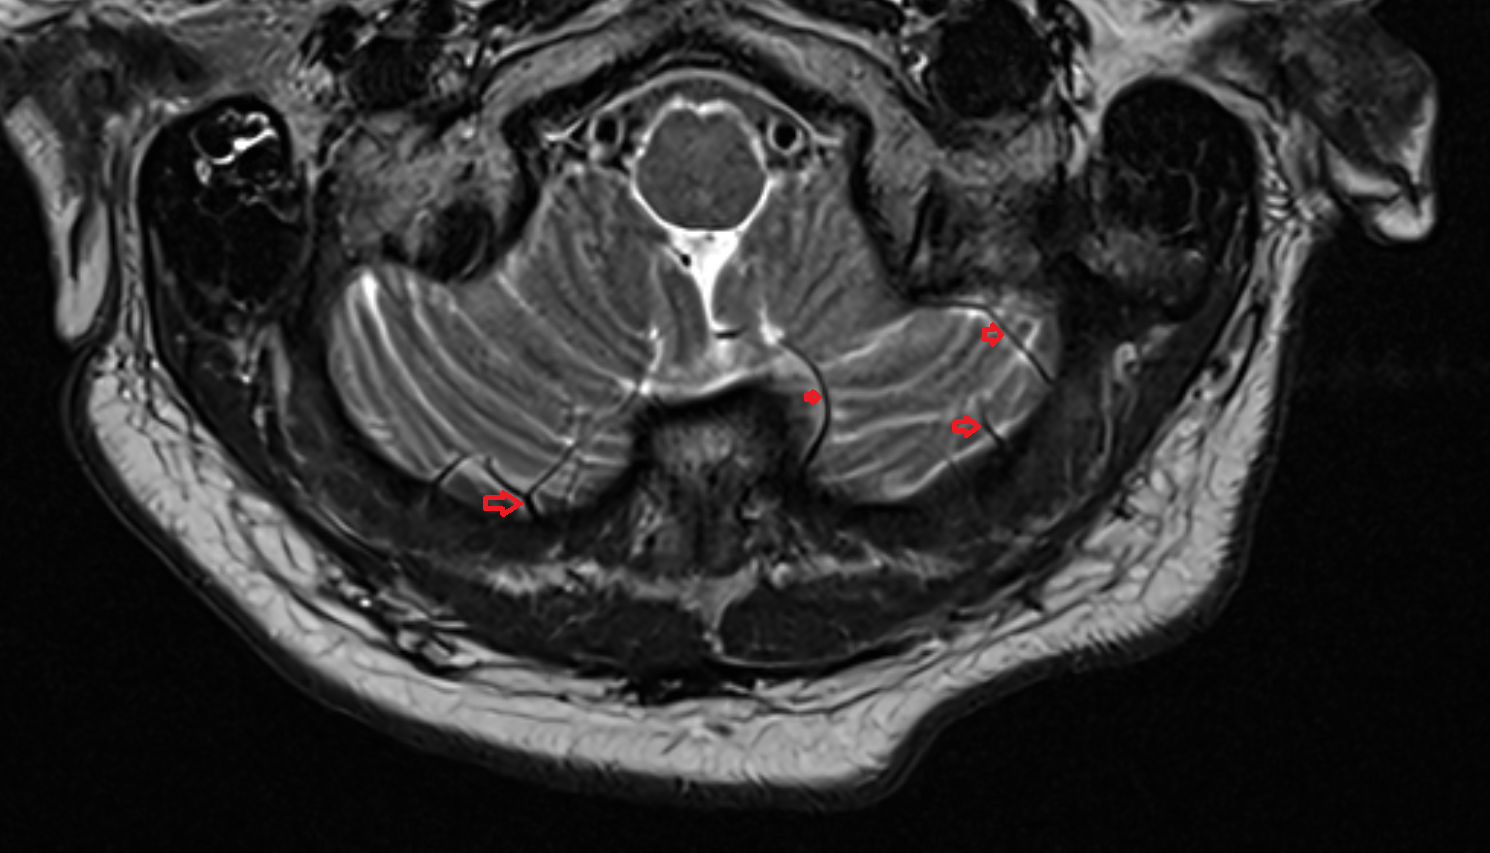

- Cerebellum

- Flocculus

- Cerebellar tonsil (H IX)